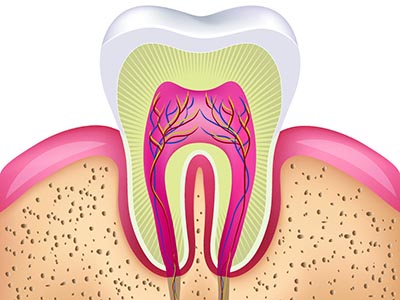

- 牙髓炎是日常生活中经常见的一种疾病,通常牙髓炎疼痛时会沿三叉神经分布区放射到同侧的上下牙及 头面部,因此患者常有半侧的头痛、太阳穴痛的情况,是非常难受的。因此很多人都想摆脱牙髓炎的困 扰,那么南京牙髓炎治疗一颗多少钱?

一、牙髓炎治疗需要多少钱?南京康贝佳口腔医生介绍说治疗牙髓炎的费用是因人而异的,每个人的牙齿情况不同,所适合的治 疗方法也不一样,费用也是不同的,影响牙髓炎治疗费用的因素是多方面的。二、影响牙髓炎治疗费用的因素:1.患者本身的牙齿基础条件;牙髓炎的程度和治疗费用是呈正比的。2.医院的软硬件设施;3.医生的操作术;4.不同的治疗方法费用也是不同的。

一、牙髓炎治疗需要多少钱?南京康贝佳口腔医生介绍说治疗牙髓炎的费用是因人而异的,每个人的牙齿情况不同,所适合的治 疗方法也不一样,费用也是不同的,影响牙髓炎治疗费用的因素是多方面的。二、影响牙髓炎治疗费用的因素:1.患者本身的牙齿基础条件;牙髓炎的程度和治疗费用是呈正比的。2.医院的软硬件设施;3.医生的操作术;4.不同的治疗方法费用也是不同的。